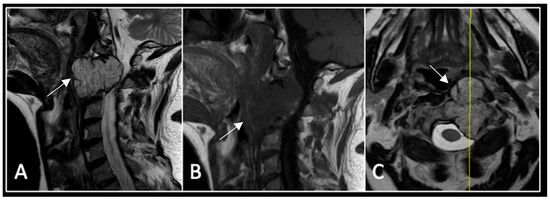

A 73-year-old male presented with an eight-month history of neck pain that was exacerbated on lying flat. He denied any symptoms of myelopathy and radiculopathy. He did not have any constitutional symptoms of malignancy. Past medical history included hypertension, renal cysts, and an ascending thoracic aneurysm. Examination was unremarkable. Diagnostic whole-spine MRI imaging demonstrated a large lobular mass localised to the cervical spine (Figure 2). Biopsy confirmed a conventional chordoma, and he underwent separation surgery followed by adjuvant proton beam therapy. Postoperative surveillance imaging at 12 months demonstrated stable disease (Figure 3).

Figure 2.

MRI demonstrating a destructive lobular lesion localised to the C2 vertebra (chordoma) (arrow). There is significant left-sided extension into the paravertebral tissues laterally and epidural space centrally with indentation of the cord. The yellow line on the sagittal images denotes the level at which the corresponding axial section was obtained. (A) T2-W sagittal; (B) T1W sagittal; (C) T2W axial.